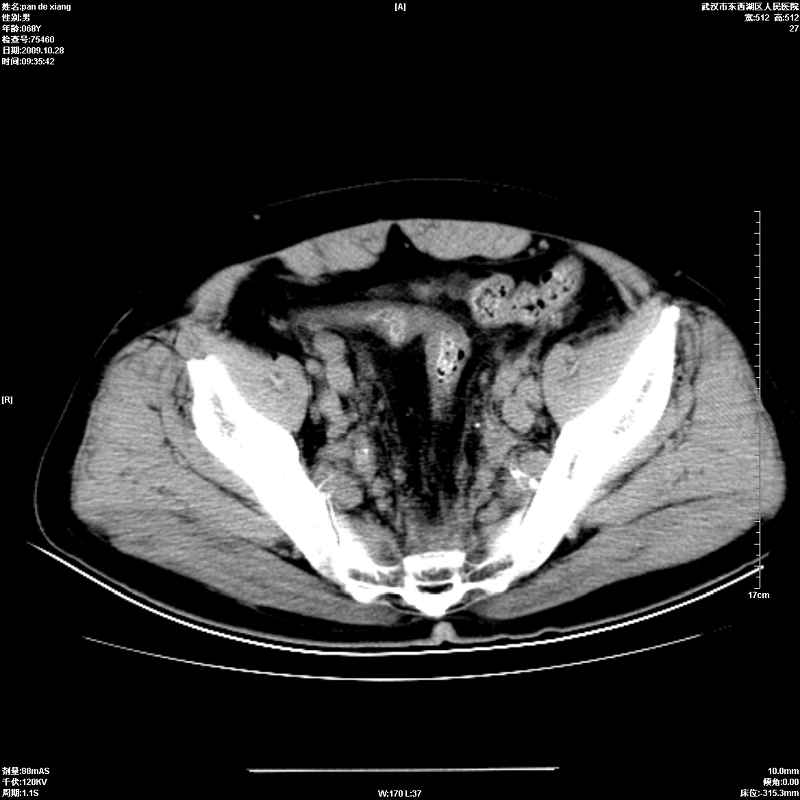

以下是引用杀毒软件在2009-10-28 20:41:00的发言:[br]结合临床考虑---白血病双肾改变或淋巴瘤。

以下是引用zxl51642在2009-10-29 9:59:00的发言:[br]结合临床“单克隆免疫球蛋白血症”,考虑双肾为继发损害并肾功能不全(尿中大量igg及少量iga、igm等大分子免疫球蛋白滤出所致继发损害),椎前软组织肿块为髓外造血。与浆细胞瘤有区别,平扫时有战友说的很清楚。